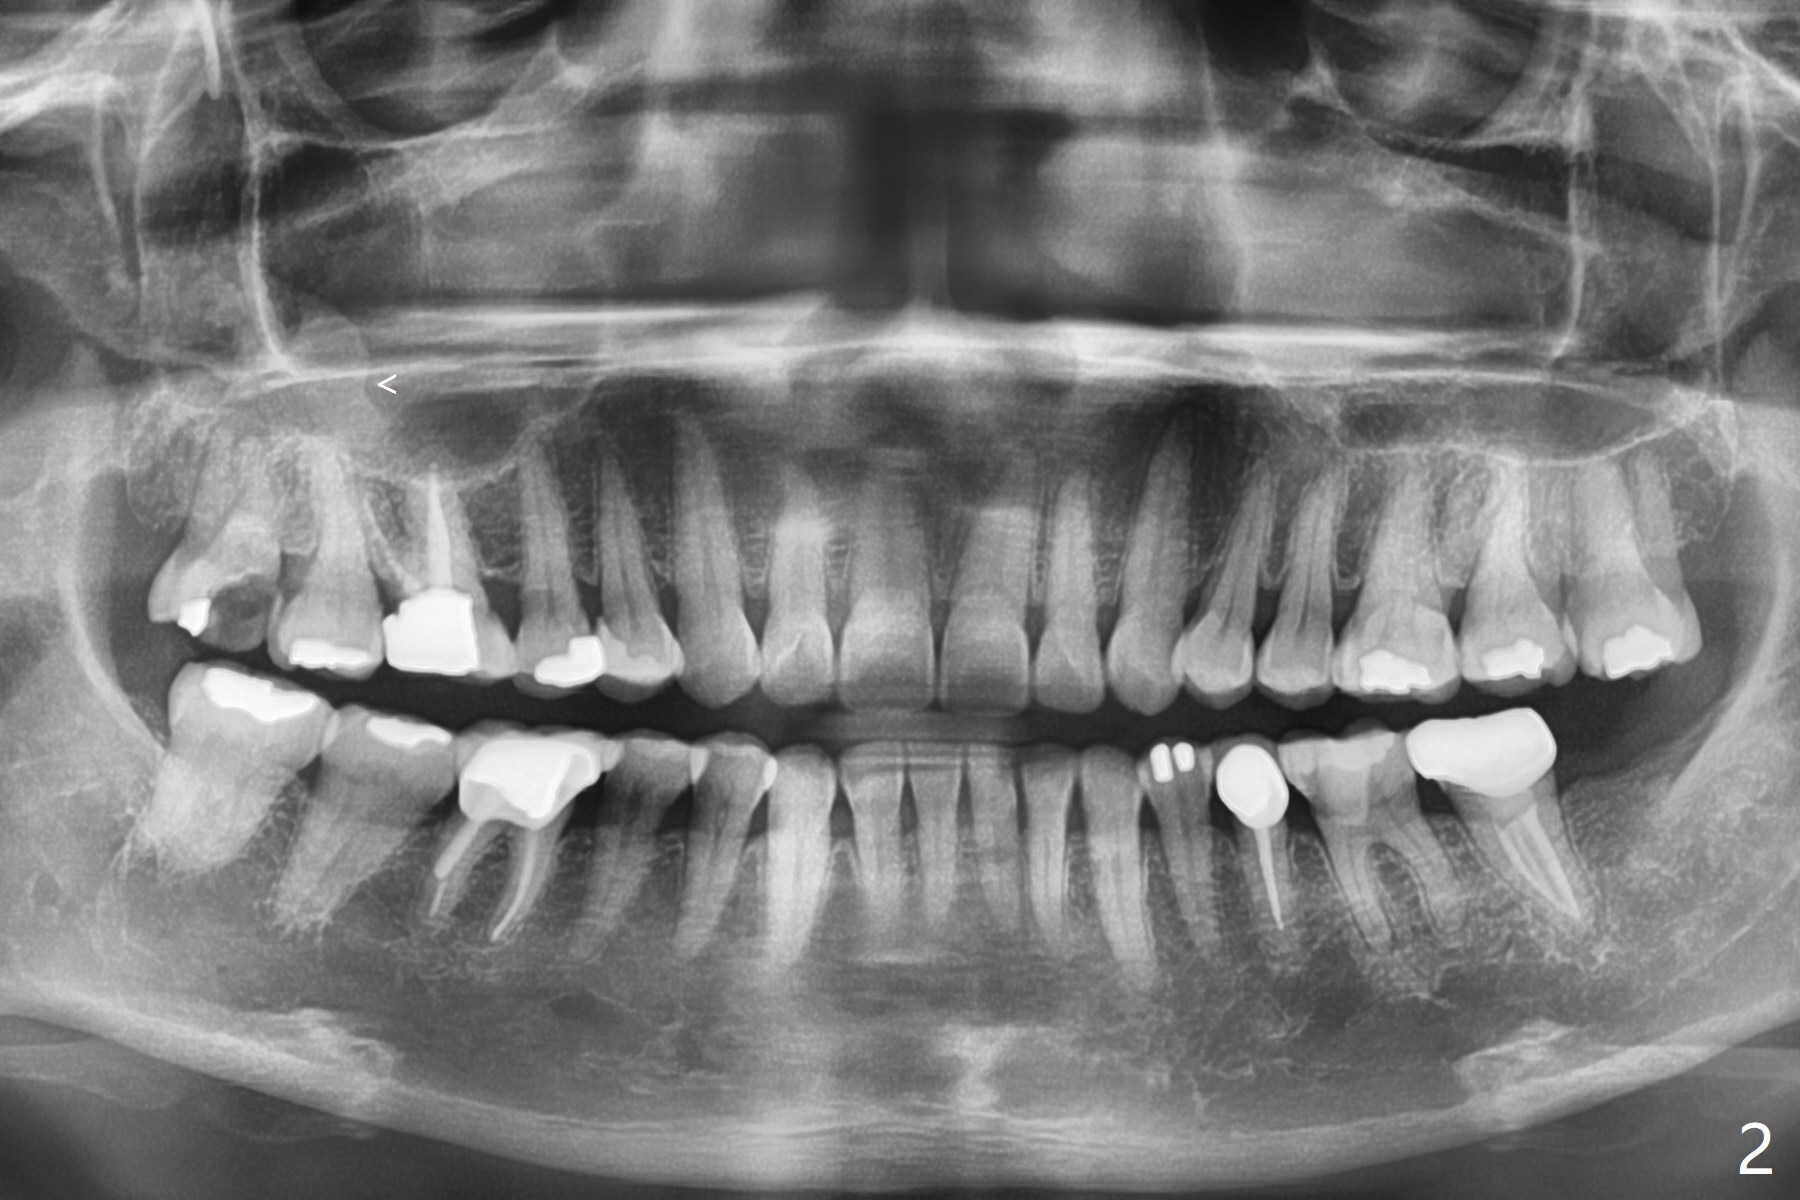

智齿与上颌窦囊肿

54岁女右上智齿银汞充填物(图一)脱落(图二),要求拔除,智齿无叩痛,仔细观察发现5.5年前根尖阴影(图一),现在根尖阴影以及上颌窦囊肿(图二:<)。准备向医疗保险申报CT,截骨(osteotomy),囊肿切除术,PRF。